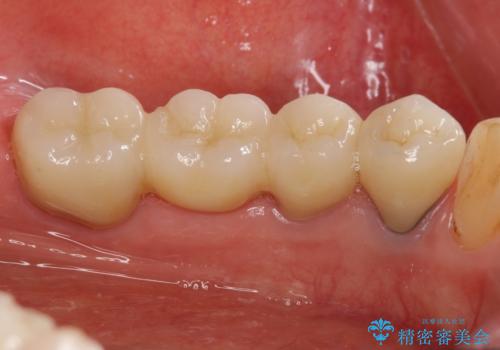

- 上下1本づつの歯を失い、噛めないことの改善を求めて来院されました。

保存可能な歯の虫歯・根管治療を行い、喪失した部分はインプラントを埋入、オールセラミックジルコニアクラウンを製作し審美的に仕上げていきます。

- 120万円(仮歯×6・ファイバーコア×2・ジルコニアクラウン×6・インプラント×2・チタンカスタムアバットメント×2)費用は治療当時の料金となります

今回下顎の欠損部位はブリッジも検討されましたが、並行性の観点から最後方臼歯の神経を取るリスクを抑えるためインプラント治療を選択しました。